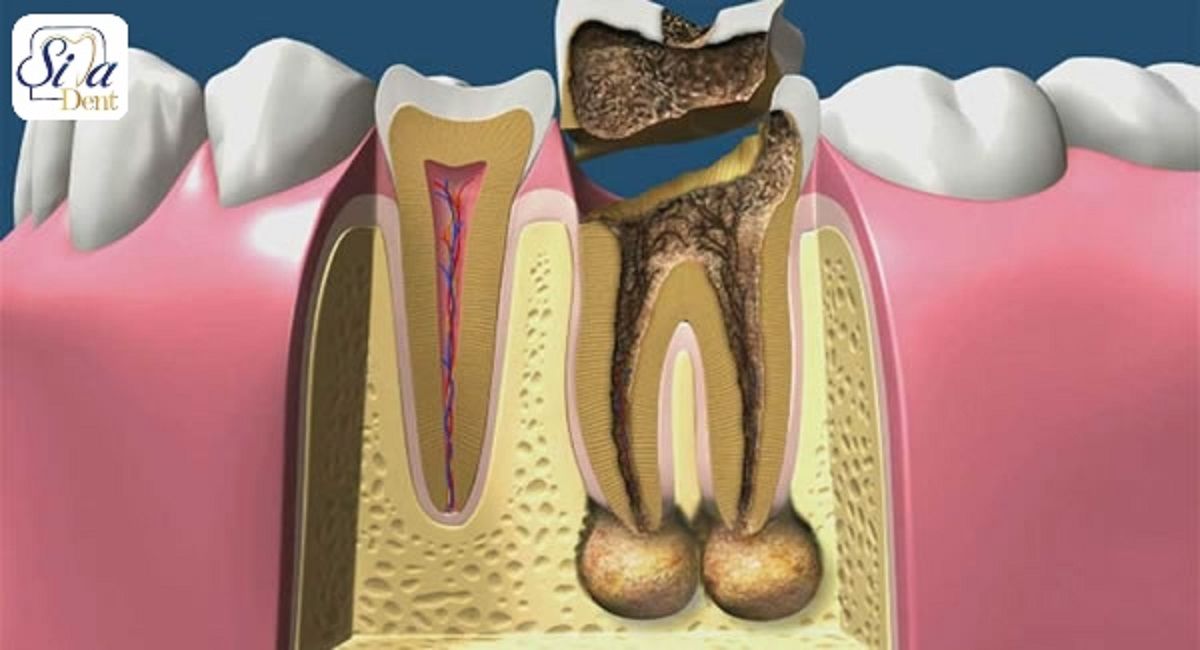

Причиной периодонтита могут быть инфекция, травма, действие токсичных веществ. Чаще периодонтит является исходом кариеса или пульпита, при котором пульпа (нерв) уже не может служить барьером для токсичных продуктов и они проникают за верхушку зуба. Периодонтит как и пульпит в большинстве случаев развивается на начальных стадиях практически незаметно, зачастую после острого воспаления пульпы и при отсутствии соответствующего лечения.

При длительном течении процесса околоверхушечная костная ткань постепенно разрушается, образующийся дефект замещается грануляционной тканью.

В одних случаях у больного вокруг грануляционной ткани образуется плотная фиброзная капсула — зубная гранулема, которая со временем может превратиться в кисту, заполненную гноем и продуктами воспаления.

В других, возникает очаг, постоянно генерирующий гной, что приводит к формированию на десне в области проекции корня больного зуба длительно функционирующего свища.

Периодонтит является следующей стадией развития пульпита.

Воспаление периодонта возникает от многих причин: в результате осложнения пульпита или его непрофессионального лечения, поражения, в результате травмы или длительного воздействия препаратов, содержащих мышьяк, на зубную полость.